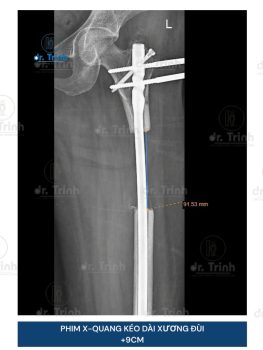

Dr.Trình Và Bước Đột Phá Trong Phẫu Thuật Kéo Dài Xương Đùi

ThS.BS Lê Khánh Trình (Dr.Trình), bác sĩ phẫu thuật đầu tiên thực hiện phẫu thuật...